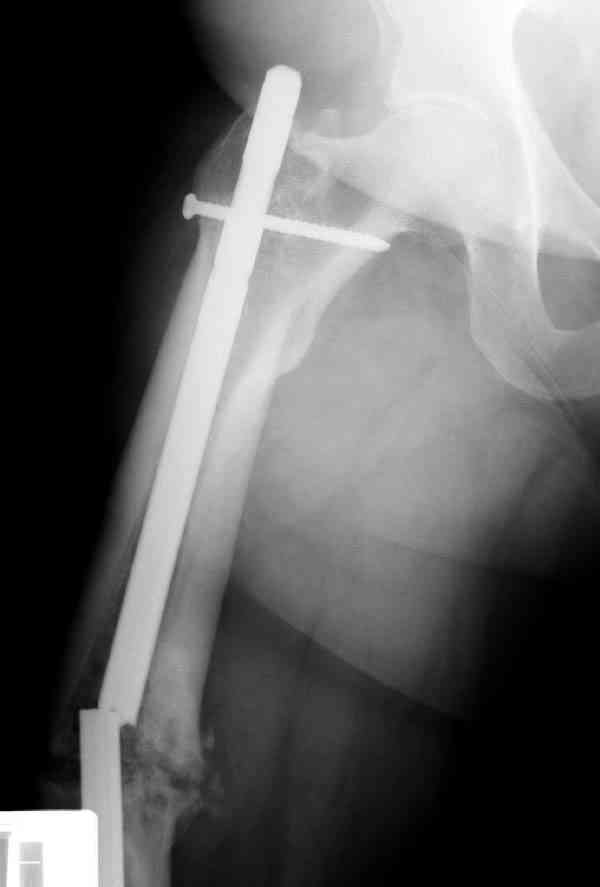

Уважаемые коллеги! У пациента 50-ти лет ложный сустав голени, перелом интрамедуллярного штифта. Перелому около 2 лет, ходить с полной нагрузкой начал через 3 мес. после операции. Боли при ходьбе почувствовал около 2 мес. назад. На данный момент ходит с полной нагрузкой без посторонней опоры. Среди коллег развернулась дискуссия по поводу способа оперативного лечения: -удаление штифта с перештифтовыванием блокированным штифтом с рассверливанием и остеотомией м\б кости -стабилизация зоны ложного сустава по медиальной поверхности LCP-пластиной с декортикацией или без -удаление штифта или без и синтез в АВФ с декотрикацией или без и остеотомией м\б кости

уважаемый коллега! Здесь имеется типичный тугой ложный сустав б/берцовой кости. У нас бы удалили старый стержень, реостеосинтез более толстым стержнем с рассверливанием с блокированием в динамическом варианте. Проблема будет с удалением дистального отломка стержня. Здесь на форуме это вопрос уже рассматривался неоднократно. Поищите по поисковику.Вот здесь, кажется http://weborto.net/forum/1164105478/, http://weborto.net/forum/1192794837

Все перечисленные варианты способны привести к желаемому результату. Несращение здесь - результат нестабильности, так что любой вариант

стабилизации решит проблему. Одного безоговорочно лучшего нет, у всех есть плюсы-минусы.

Наиболее быстро достичь опорности без боли и внешних приспособлений - удаление и блокируемый реостеосинтез с рассверливанием. Лучше бы тоже с

восстановлением оси (отклоняющая спица в дистальном отломке, чтобы новый стержень прошел не в старый канал, а кзади от него), еще и для создания дополнительного напряжения тканей в области несращения. Открывать зону несращения не надо.

Сросшаяся малоберцовая как распорка привела к образованию ложного сустава. В таких случаях удаляем сломанный штифт и проводим стимуляцию ложного сустава рассверливанием. Рассверливание канала создает стимуляцию на месте ложного сустава, и динамический вариант блокировки штифта с большим диаметром создаст стабильность. Ранняя нагрузка после остеотомии малоберцовой приведет к сращению ложного сустава.